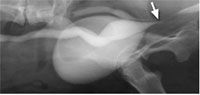

Urolithiasis commonly affects dogs and can cause dysuria, stranguria, hematuria, pyuria, and an obstructive uropathy.

Upper tract uroliths have been relatively rare in cats until the last ten years.

Over the last several years, there has been a shift in the mineral content of uroliths in cats from predominantly magnesium-ammonium phosphate to calcium oxalate.